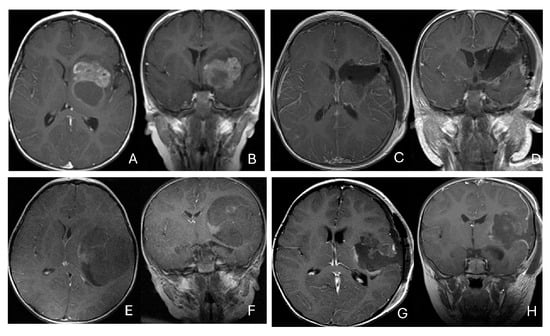

Only one case involved an intramedullary tumor located in the cervical cord of a 34-month-old girl (Figure 11A–D). Two patients, a 64-month-old girl and a 96-month-old girl, had intradural extramedullary tumors situated at the T12-L1 and L3-S2 levels, respectively. Additionally, a 7-month-old girl presented with a contiguous intradural extramedullary and extradural tumor that extended outward to the paraspinal structures (Figure 11E–I). She underwent a staged operation, initially through a cervical laminoplastic laminotomy at the C5–7 level, followed by a second surgery via an anterior cervical approach for the total resection of the extraspinal disease after chemotherapy.

Figure 11.

Spine ATRT. (A–D): MR images ((A), sagittal; (B), axial) of a 34-month-old girl show a heterogeneous intramedullary cervical tumor centered at C3–C5. Postoperative images ((C), sagittal; (D), axial) demonstrate gross-total resection. (E–I): T2-weighted sagittal MR (E) and post-contrast axial MR (F) of a 7-month-old girl show a C5–C7 intradural–extramedullary ATRT with extradural and extraspinal extension (open arrow). The intradural–extramedullary component from the C6 dorsal nerve root and the epidural component into the neural foramina were resected (G), sagittal; (H), axial through a laminoplastic laminotomy, note a persistent paraspinal tumor (open arrow). Following chemotherapy, the residual paraspinal component was subsequently resected via an anterior cervical approach ((I), axial). (J–M): Mid-thoracic MR images ((J), sagittal; (K), axial) of a 9-year-old boy show a dorsal epidural ATRT from T7 to T9 with right-sided neural foraminal extension (arrow). An epidural ATRT was removed through laminectomy ((L), sagittal; (M), axial).

Another child, the oldest in this cohort, was an 11-year-old boy who presented with a dumbbell-shaped intradural extramedullary ATRT extending into the extradural space and neural foramina at the C5-T11 levels. Additionally, a 9-year-old boy had ATRT located in the epidural space, extending into the neural foramina at the T7–9 levels (Figure 11J–M).